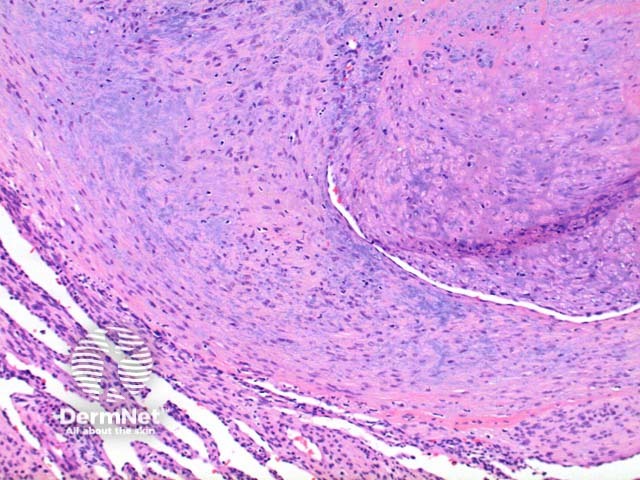

Low power view of myofibroma demonstrates a well defined multinodular tumour arising in the deep dermis or subcutis (Figure 1). Also at low power a branching ‘staghorn’ like pattern of blood vessels can be seen between the tumour nodules (Figure 2). Areas of calcification can often be seen (Figures 2, 3 and 5). The tumour nodules are comprised of a spindle cell proliferation with short plump nuclei (Figures 4,5 and 6). A basophilic tinge in the spindled peripheral component of the nodules is evident (Figures 7 and 8). Sclerotic collagen in the centre of the tumour nodules gives a biphasic appearance to the tumour (Figure 9).

Myopericytoma: There is significant overlap with this tumour and they may fall along a spectrum. A concentric perivascular proliferation favours myopericytoma, whereas a biphasic appearance with hyalinised paucicellular areas favours myofibroma.